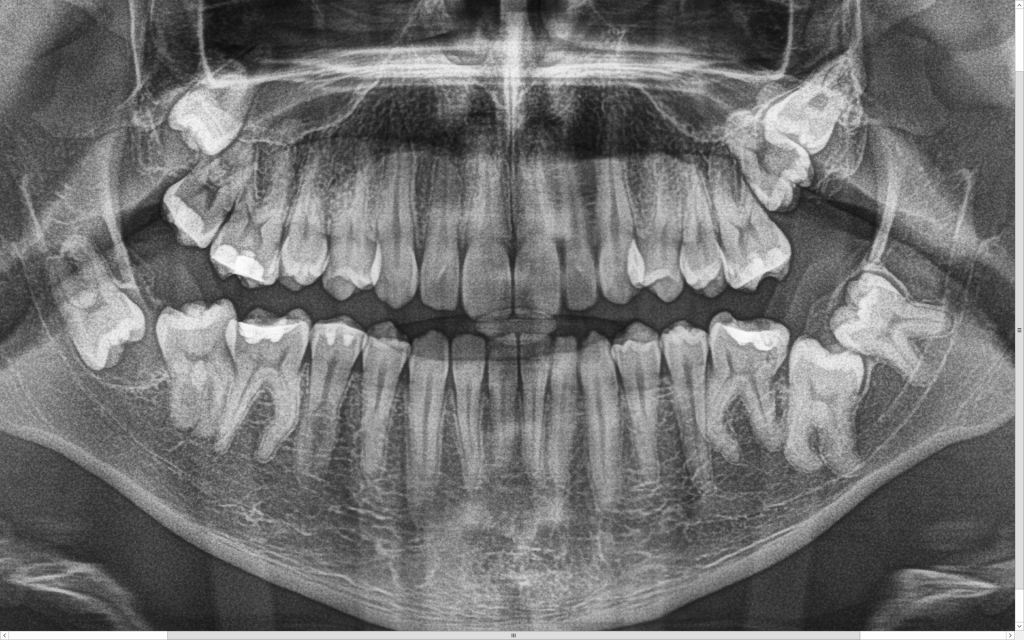

Z uwagi na moją specjalizację kierowani są do mnie pacjenci z tzw. zębami mądrości – ósemkami, które ze względu na ułożenie w kości wymagają operacyjnego usunięcia. Zdarzają się również pacjenci z mezjodensami (fot. 1,2) zębami nadliczbowymi np. dziewiątkami (fot.3), zębami zatrzymanymi (fot 4.), lub zębami zrośniętymi (fot. 5,6). Stomatolog z długą praktyką nie raz w swojej karierze zetknął się z takimi przypadkami.